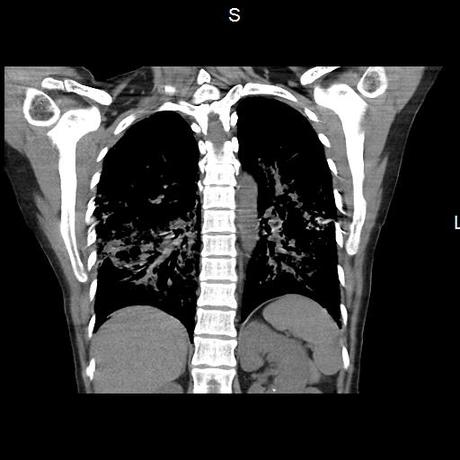

Se realiza volumen de tórax en fase simple, desde los opérculos torácicos hasta los hemidiafragmas, observándose:

El parénquima pulmonar con areas parcheadas difusas en vidrio despulido combinadas con otras areas hipodensas de baja atenuación debidas a atrapamiento aéreo y engrosamiento intersticial y zonas de fibrosis de predominio en lóbulos medios e inferiores de ambos pulmones.

- LOS HALLAZGOS PUEDEN ESTAR EN RELACIÓN A NEUMOPATIA INTERSTICIAL PROBABLE ETIOLOGIA HIPERSENSITIVA VS AUTOINMUNE/BACTERIANA/FUNGICA.